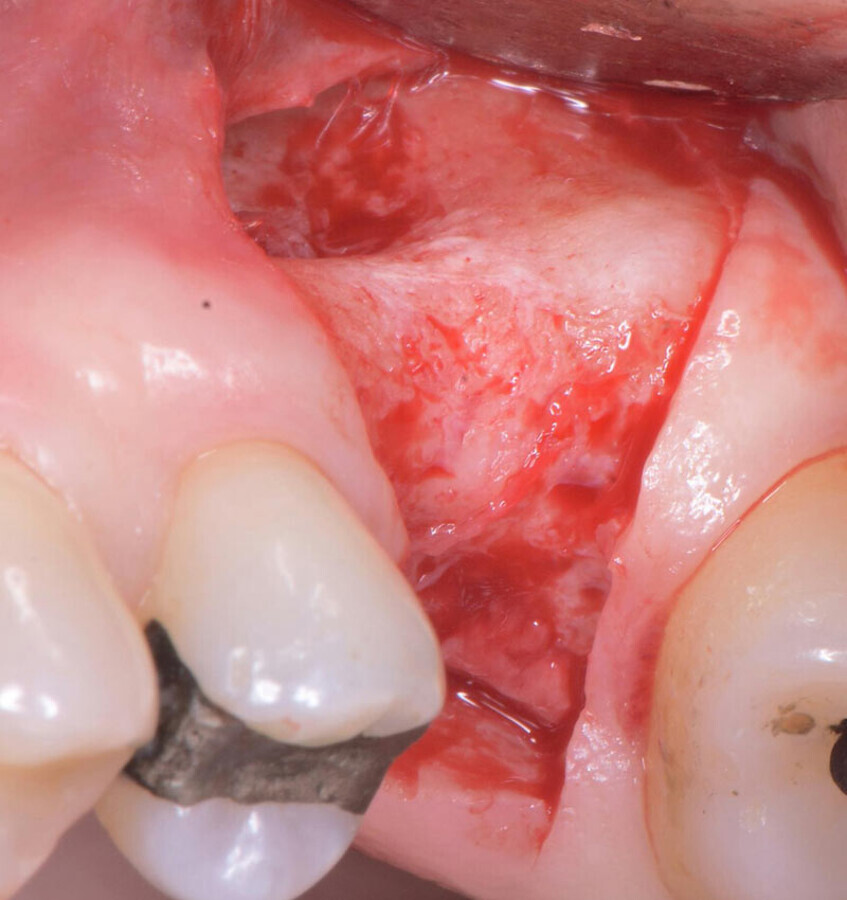

Buccal defect, need to raise a flap.

Site-specific papilla-sparing flap.

Buccal concavity.